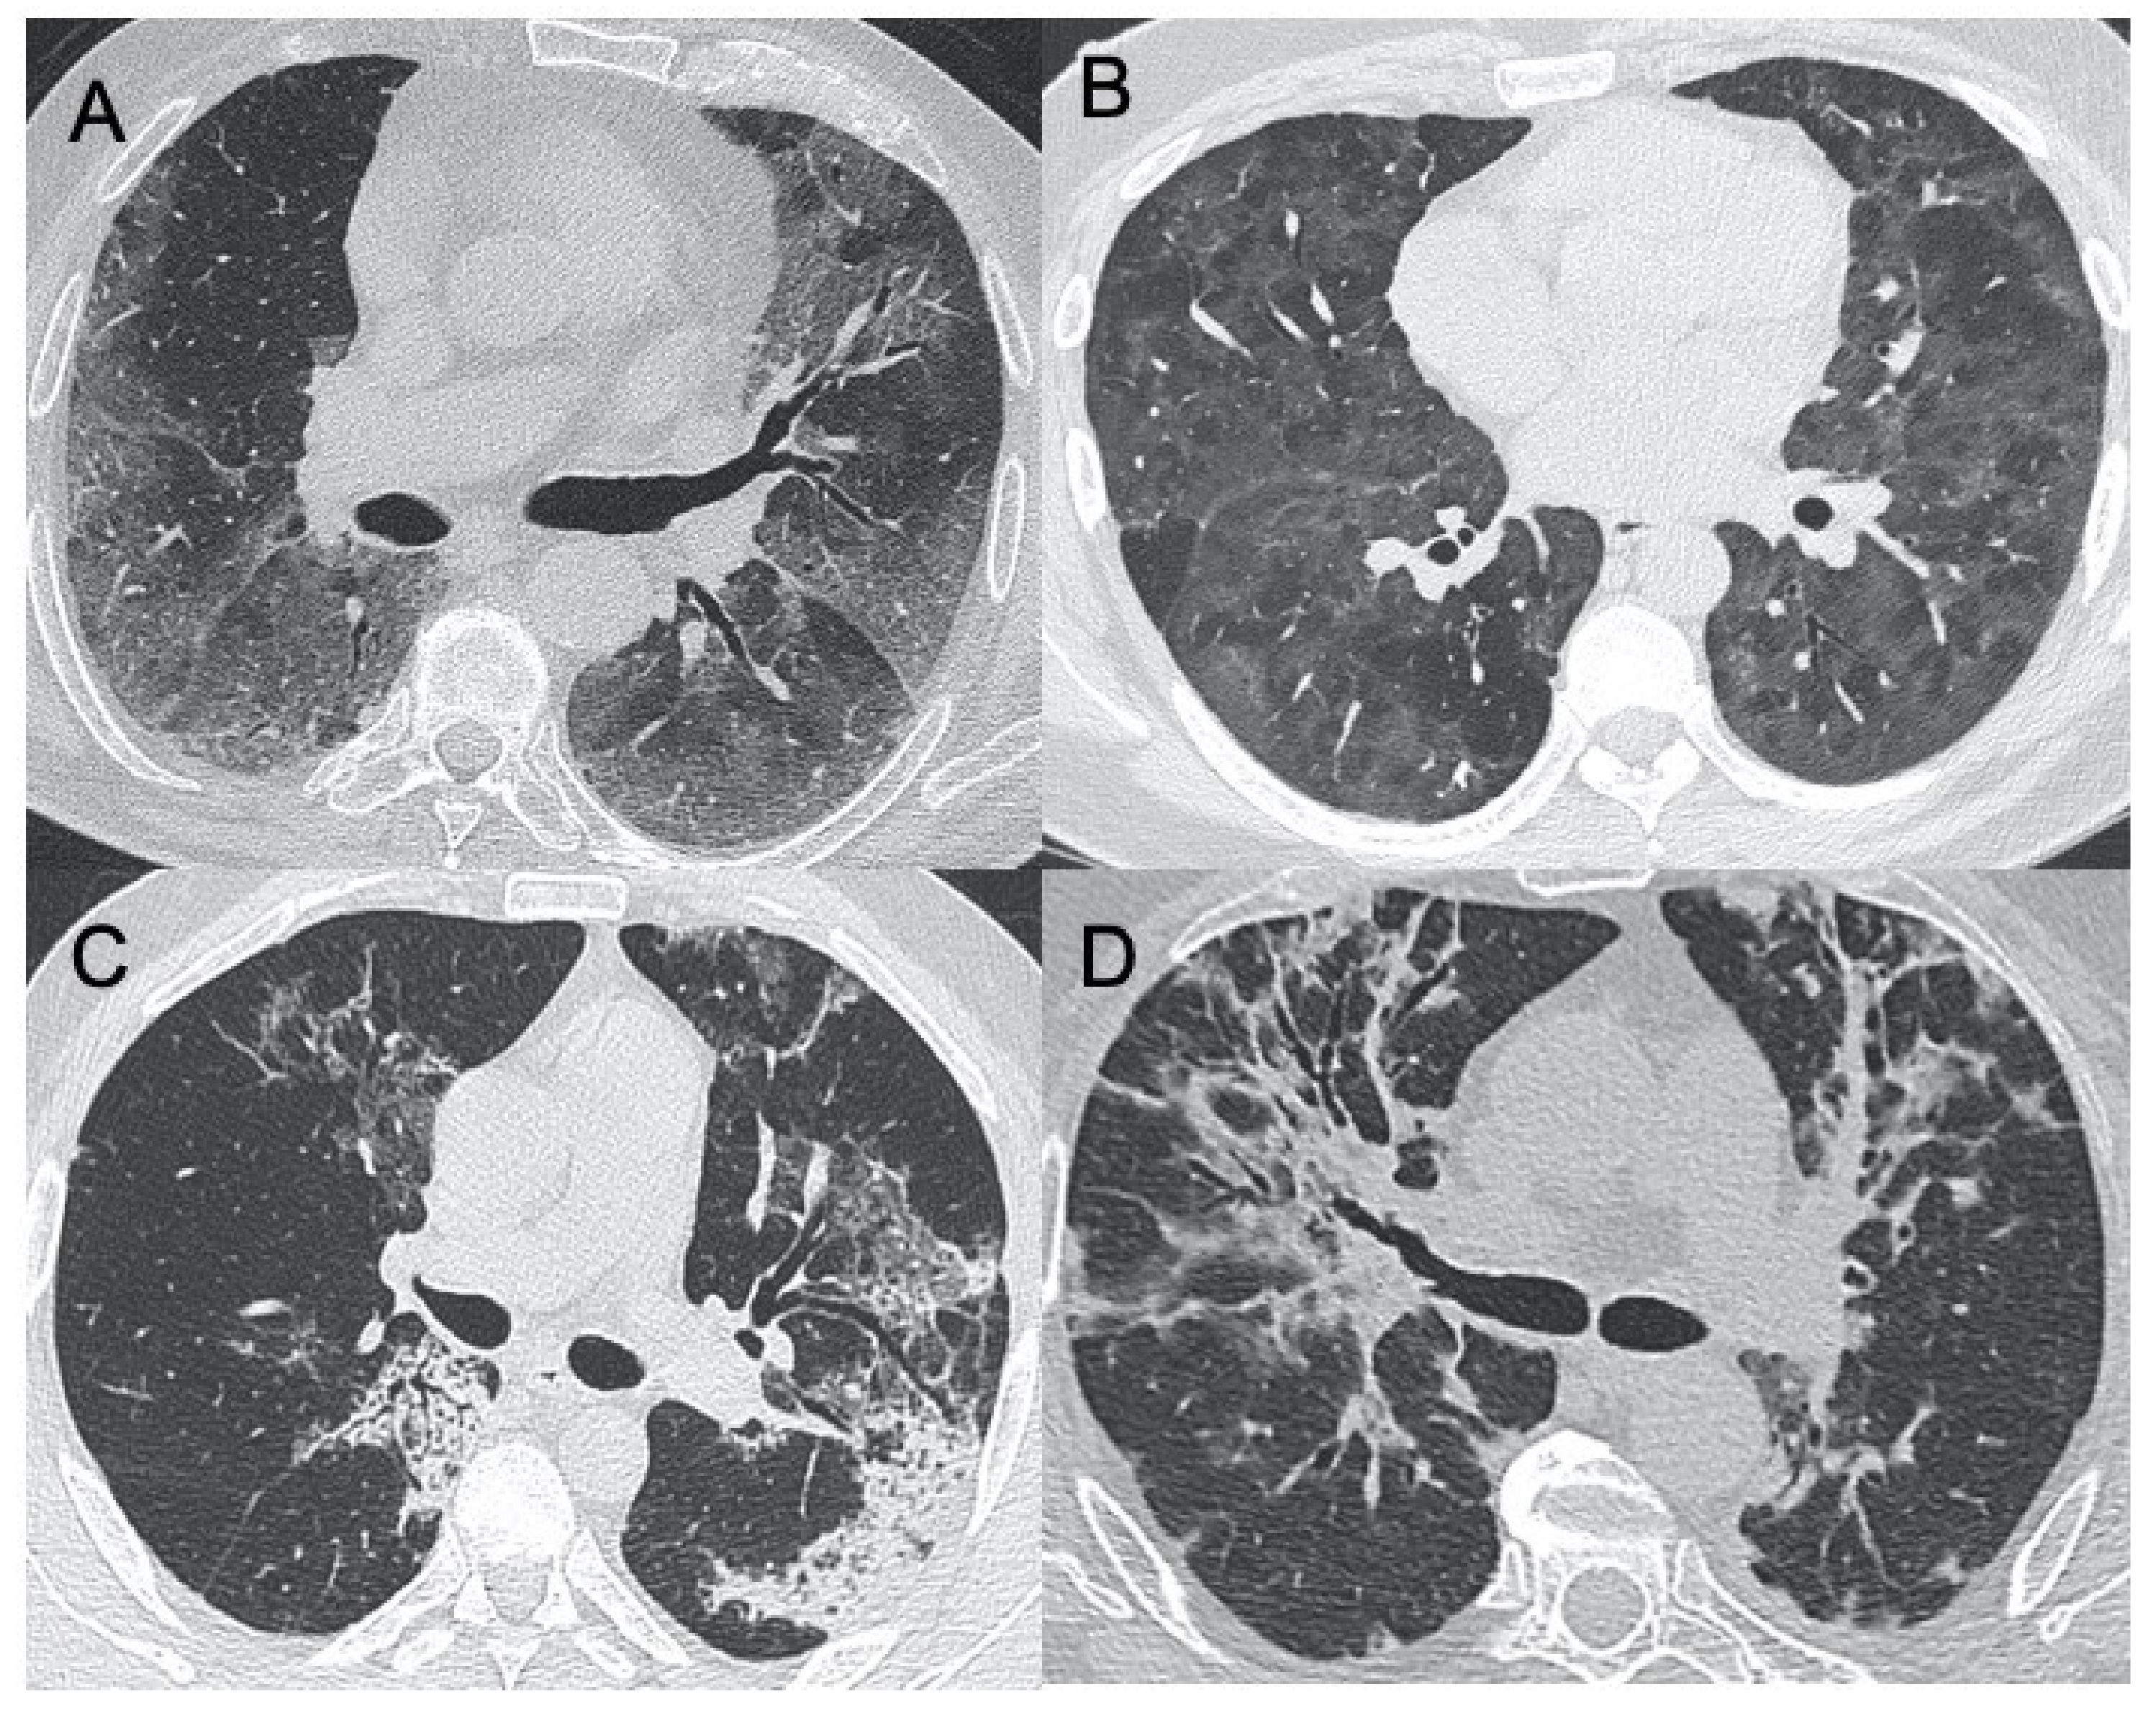

| Sars-CoV-2 | Lung subpleural consolidations, ground-glass opacities, nodules and reticular–nodular opacities, manifesting as interstitial pneumonia with diffuse alveolar damage | In the early phase, predominantly peripheral, bilateral GGOs, in association with limited consolidations, interlobular and intralobular septal thickening creating a “crazy-paving” pattern. Air bronchograms, vascular enlargement, halo sign, and reverse halo sign are also reported | Figure 1 and Figure 2 |